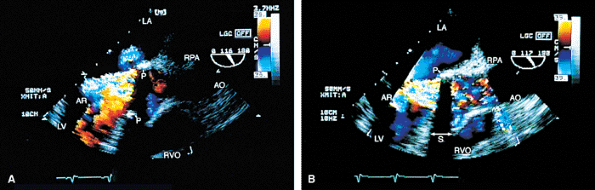

FIGURE 5.39. Porcine aortic prosthesis: valvular and paravalvular regurgitation. A. Prolapse (arrowhead) of a thickened and degenerated prosthesis (P). B–D. Aortic regurgitation (AR) flow signals are shown moving into the left ventricular outflow tract (LVOT) posteriorly from beyond the confines of the prosthesis, indicative of a paravalvular leak. C. Associated valvular regurgitation originating from within the confines of the aortic prosthesis. An anterior paraprosthetic leak is also demonstrated (white arrow). The black arrows in B and C show the site of the posterior paravalvular leak. E. Another patient with heterograft prosthesis (P) cusp prolapse demonstrating severe AR.LA, left atrium; LV, left ventricle; PA, pulmonary artery; RA, right atrium, RV, right ventricle; RVO, right ventricular outflow tract. |